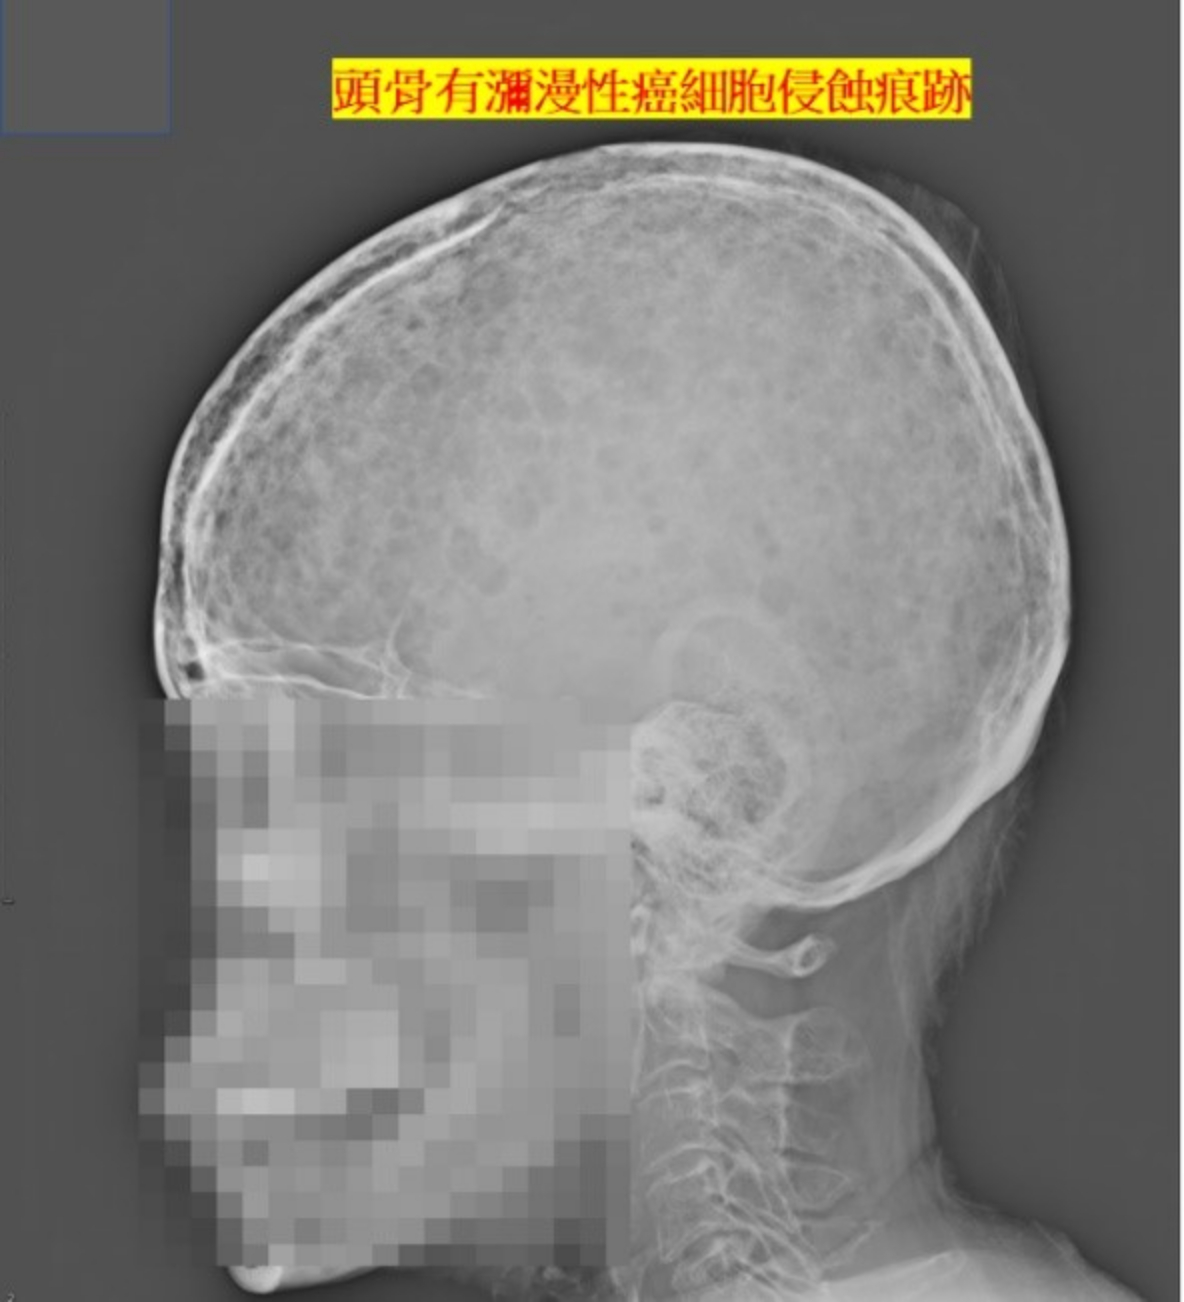

我們綜合她的臨床數據,經由縝密的思考及推理,逐漸找出她的病因,最後在血液腫瘤團隊進行骨髓切片,證實多發性骨髓瘤(multiple myeloma)的診斷。多發性骨髓瘤,是一種位於骨髓內漿細胞轉化為癌細胞並大量增生的疾病,在疾病演進的過程,會造成貧血、腎功能不全、高血鈣症、及全身性骨痛等病症。

醫學文獻中提到多發性骨髓瘤與泌尿道結石的案例不多,一般認為與高血鈣症或癌細胞分泌過多的蛋白沉積於泌尿道有關。該患者的結石經由軟式輸尿管鏡成功的清除,多發性骨髓瘤的部份由本院血液腫瘤科持續治療。